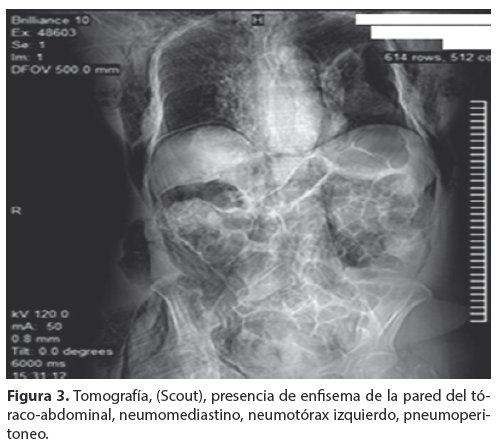

<body><![CDATA[<p align="justify"><a name="f2"></a></p>     <p align="center"><img src="/img/revistas/gmb/v37n1/a10_figura_02.jpg" width="501" height="431"></p>     <p align="justify"><font face="Verdana" size="2">La tomografía computarizada (TC); Scout (<a href="#f3">Fig. 3</a>) confirma los hallazgos anteriores, enfisema de la pared del toraco-abdominal, neumomediastino, neumotórax izquierdo, neumoperitoneo. </font></p>     <p align="justify"><a name="f3"></a></p>     <p align="center"><img src="/img/revistas/gmb/v37n1/a10_figura_03.jpg" width="503" height="448"></p>     <p align="justify"><font face="Verdana" size="2">En la TC simple de tórax en ventana mediastinica (<a href="#f4">Fig. 4</a>) se observa enfisema subcutáneo importante de la pared del tórax, neumotórax izquierdo, neumomediastino. </font></p>     <p align="justify"><a name="f5"></a></p>     <p align="center"><img src="/img/revistas/gmb/v37n1/a10_figura_04.jpg" width="498" height="343"></p>     <p align="justify"><font face="Verdana" size="2">TC de abdomen (<a href="#f5">Fig. 5</a>), se observa, enfisema subcutáneo (Es) plastrón periduodenal (Pp), pneumoperitoneo (Np) y retroneumoperitoneo (Rnp). Con la sospecha clí</font><font face="Verdana" size="2">nica e imagenológica de perforación de víscera hueca, se somete a la paciente a laparotomía exploradora de urgencia, con hallazgo de perforación del duodeno y plastrón periduodenal. Se realiza la reparación per prima, mediante duodenorrafia y evacuación de la colección y drenaje del mismo.</font></p>     <p align="justify"><a name="f5"></a></p>     ]]></body>